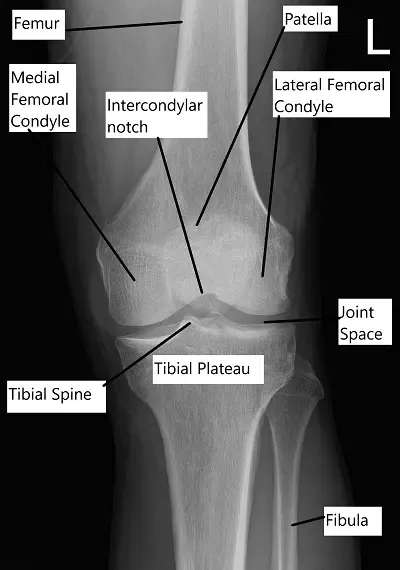

Radiografía que muestra anatomía de rodilla.

La rodilla está formada por cuatro huesos:

Fémur (fémur), tibia (espinilla), rótula (rótula) y peroné (un hueso delgado junto a la tibia).

Los extremos superiores de la tibia y el fémur forman la articulación principal de la rodilla, mientras que la rótula se sitúa al frente y se desliza al doblarla. La articulación está revestida de sinovia, que produce un líquido que nutre la articulación.